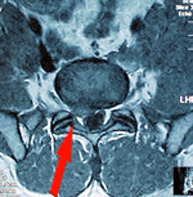

- RMN. Esta prueba es concluyente en la mayoría de los casos y además de esclarecer el

tipo, situación de la hernia descarta otras lesiones tipo quiste y tumores que también son causa de ciática de forma excepcional. - TC. Cuando existan dudas es una prueba a realizar ya que aporta mejor información de las alteraciones óseas.